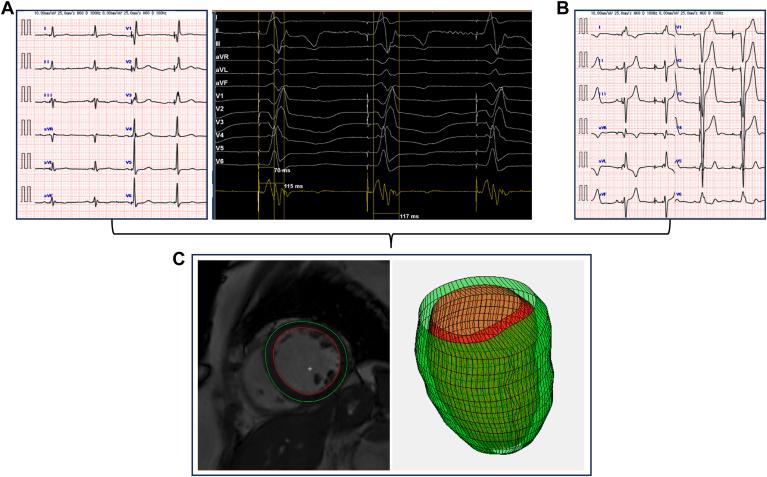

The purpose of this study was to compare the effects of LBBAP and RVP on cardiac energetics using a novel noninvasive pressure-volume (PV) loop algorithm derived from cardiac magnetic resonance (CMR).

We included patients who underwent permanent pacemaker implantation with LBBAP or RVP between January 2021 and October 2024, followed by CMR imaging. Noninvasive PV loops were calculated using volumes derived from CMR and a time-varying elastance model. The parameters obtained from the PV loop analysis were compared between the LBBAP and RVP groups. Sensitivity analyses were performed by varying the left ventricular end-diastolic pressure (3-40 mm Hg) and excluding anodal pacing cases.

Of the 235 patients, 15 were analyzed (LBBAP group, n = 7; RVP group, n = 8). The end-systolic PV relationship was significantly higher in the LBBAP group (2.25 mm Hg/mL [1.85-2.55]) compared to the RVP group (1.39 mm Hg/mL [1.33-1.69]; <.0001). The potential energy and PV area were significantly lower in the LBBAP group ( = .0006 and = .006, respectively), whereas the ventricular efficiency was significantly higher (63.1% vs 57.4%; = .006).